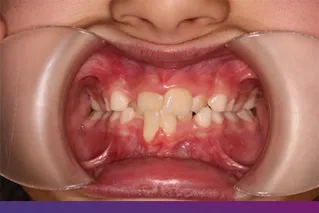

Potrivit specialiștilor, în jurul vârstei de 7 ani se pot identifica probleme de spațiu, probleme scheletice, precum și o serie de alte probleme, precum:

- Angrenaj invers

- Înghesuiri

- Ocluzie deschisă

- Ocluzie inversă/mușcătură inversă

- Spațieri

- Prodenție

Unele probleme ortodontice sunt mult mai ușor de corectat în dentiția temporară sau mixtă.